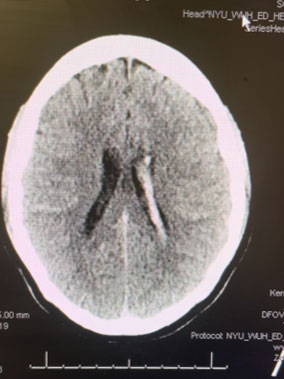

Angiogram (Figure 3 and 4) confirmed the presence of a deep left frontal AVM without any associated aneurysms.

Fig. 3